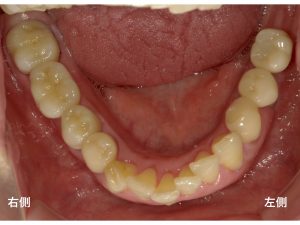

以下が治療後です。

左側のインプラント部分は、ジルコニアを使用し、

右側の奥歯もジルコニアを使用したブリッジによって治療を行いました。

審美的にも満足できる治療です。